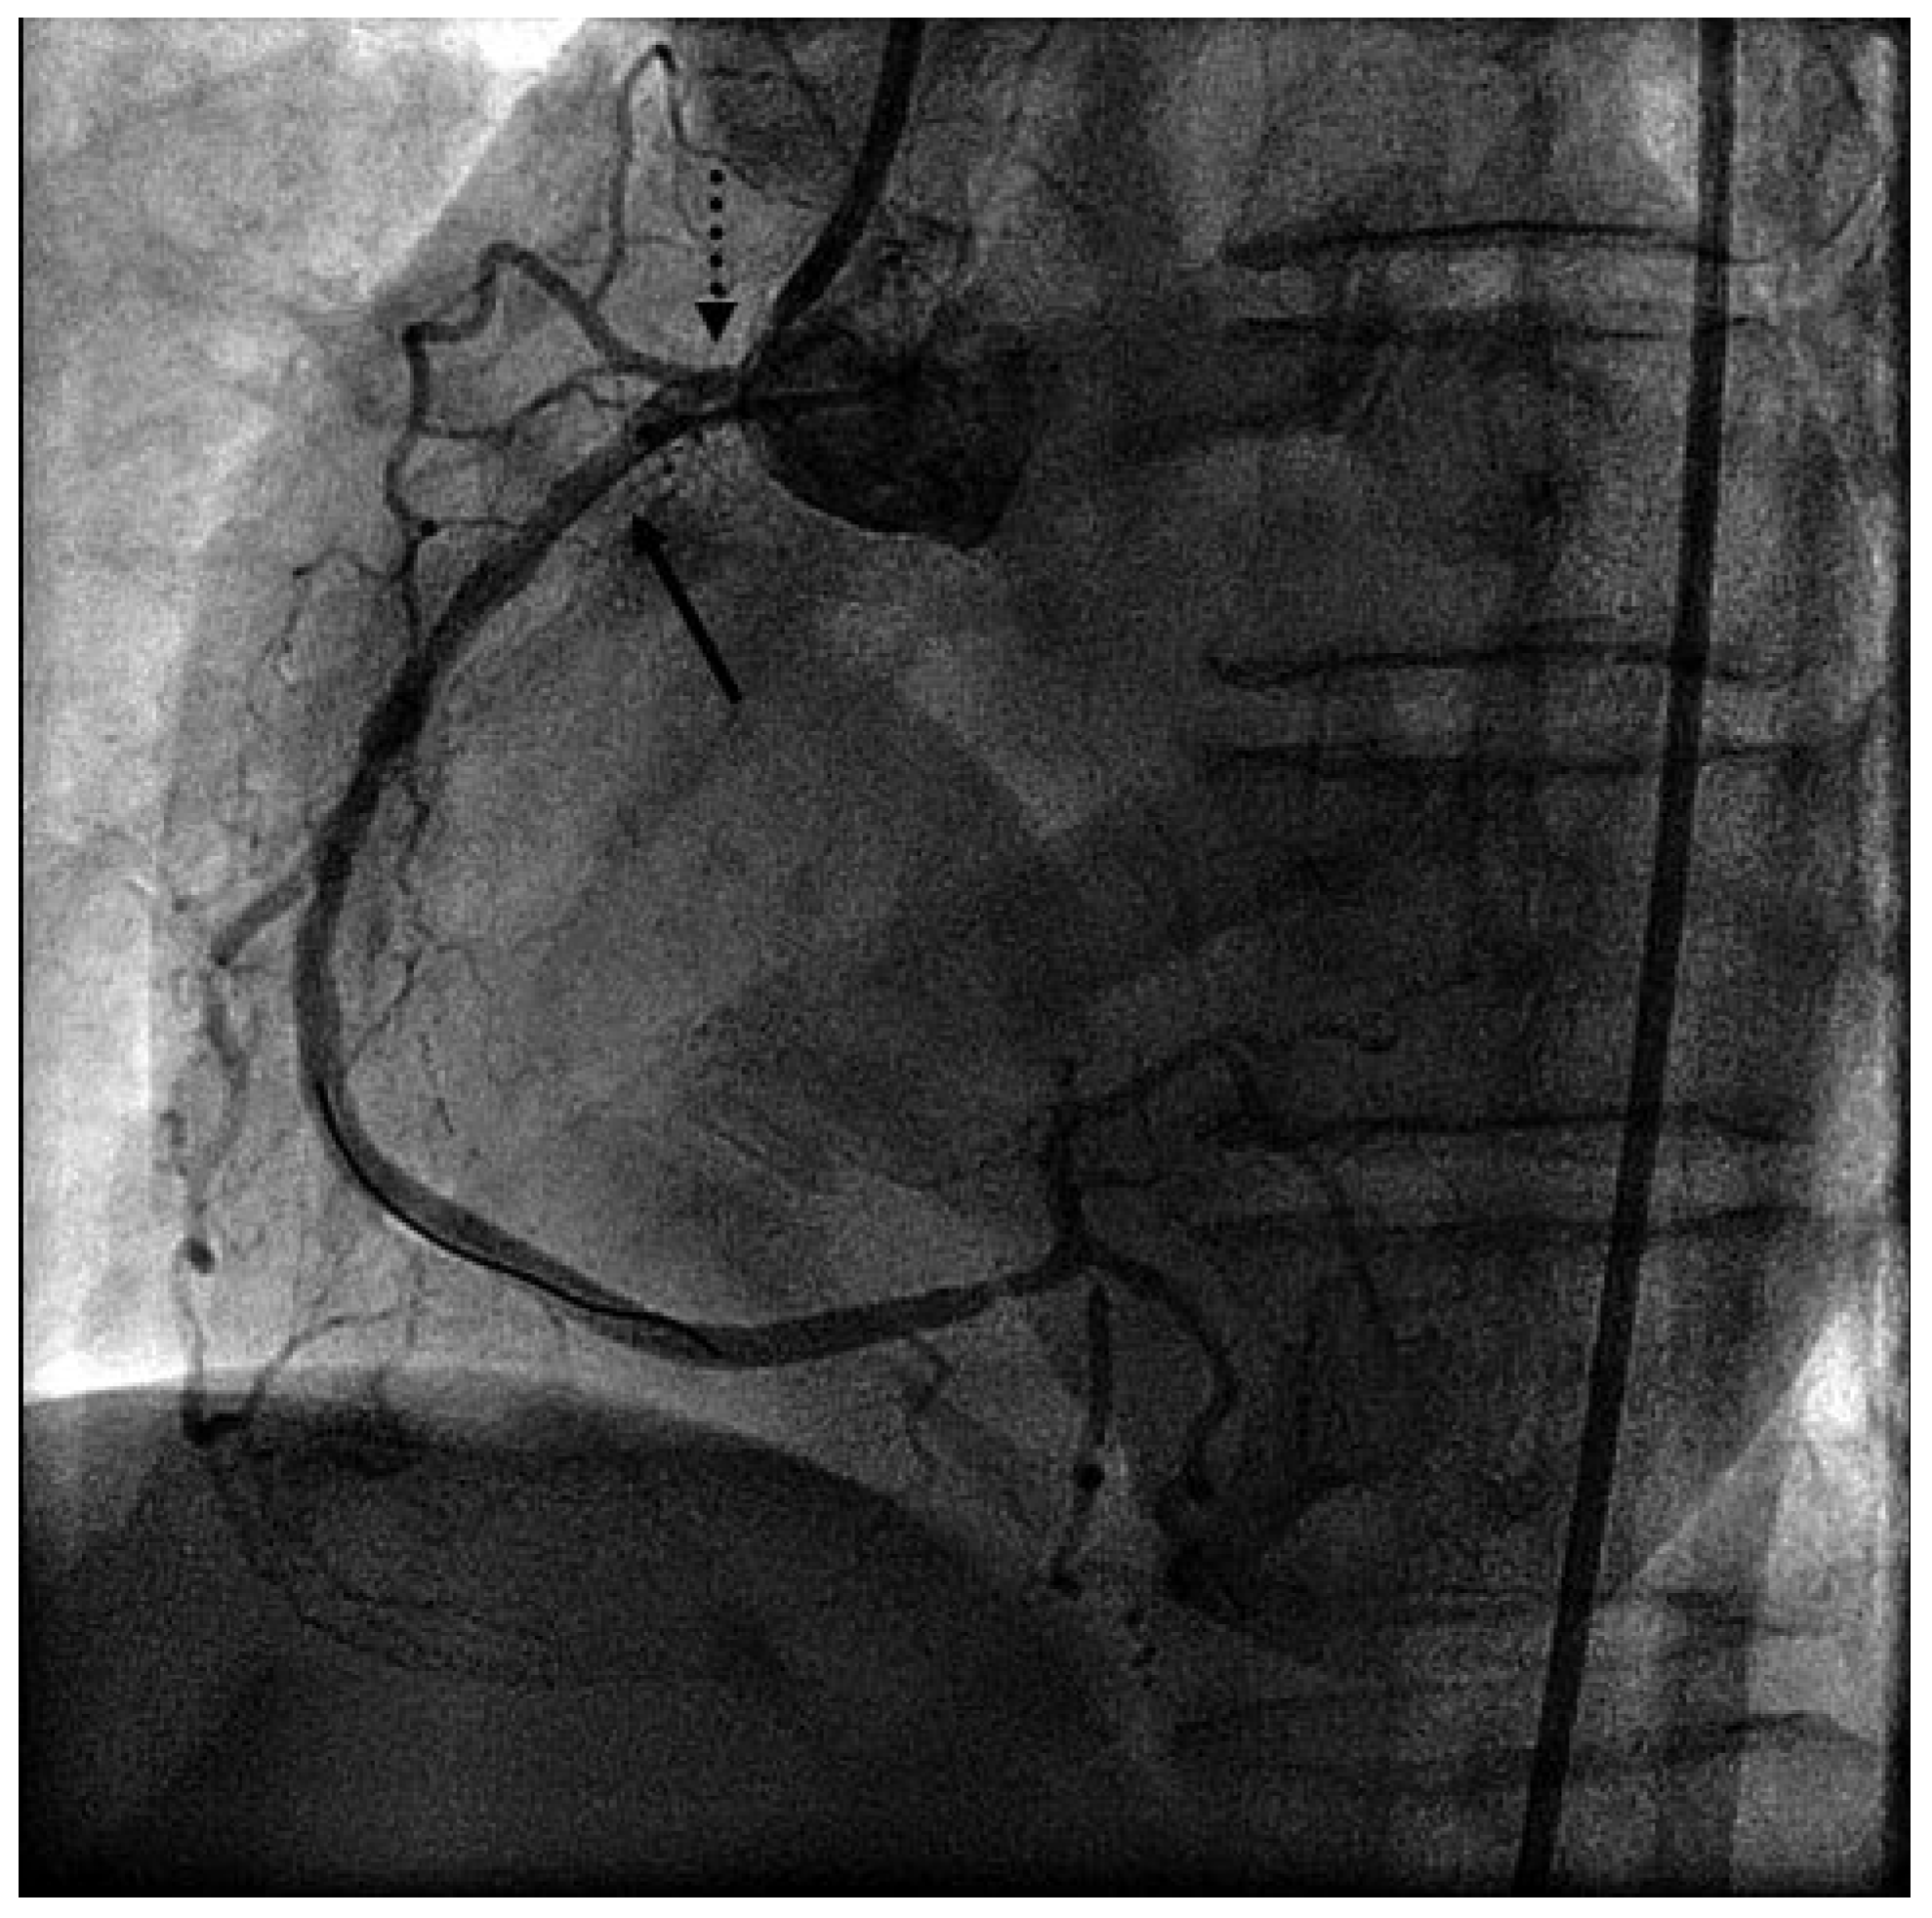

Presenting ECG changes (inferior ST-elevations) and rising cardiac enzymes, the patient was transferred to the acute care hospital and cath lab. Emergency coronary angiography showed severe stenotic lesions in the proximal right coronary artery (RCA) (Figure 1), in the proximal left anterior descending artery and in the diagonal and marginal branches. Due to cardiogenic shock and inferior ECG changes, a percutaneous coronary intervention in the RCA was organised. After engaging the RCA with the guide catheter, total occlusion of the RCA was observed. The coronary wire was immediately placed in the distal RCA but this failed to restore the flow (Figure 2).

Figure 1. Left anterior oblique (LAO) view of the RCA: significant focal stenosis of the proximal RCA (arrow) and significant ostial stenosis (dotted arrow).